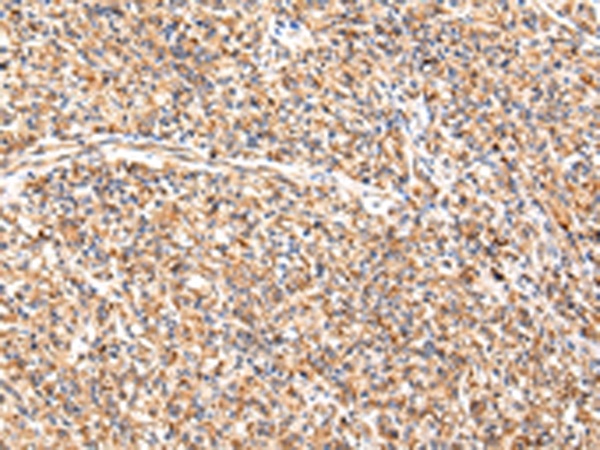

分类: 科研抗体货号: P43467别名: OF; XDP; BA2R; CCG1; CCGS; DYT3; KAT4; P250; NSCL2; TAF2A; N-TAF1; TAFII250; DYT3/TAF1; TAFII-250; TAF(II)250应用: WB,IHC反应种属: Human,Mouse